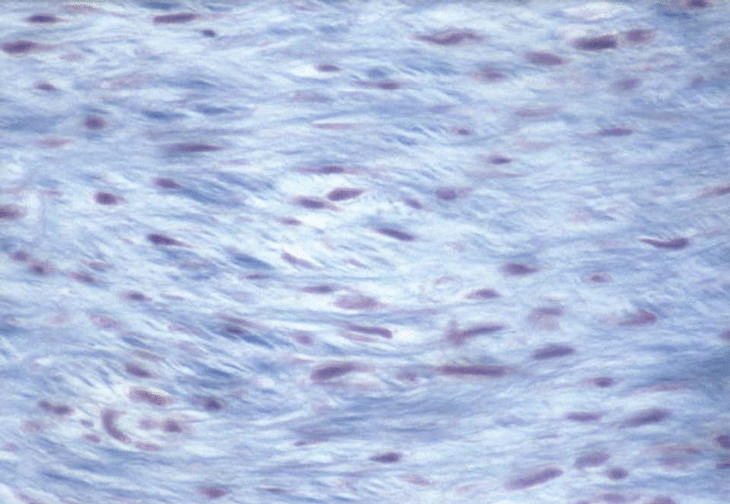

Revista Española de Cardiología es una revista científica internacional dedicada a las enfermedades cardiovasculares. La revista publica en español e inglés sobre todos los aspectos relacionados con las enfermedades cardiovasculares. Paciente de 50 años, con revisión cardiológica impracticable realizada dos años antes. En la radiografía de tórax se apreciaba ligera cardiomegalia, con signos de peso alveolointersticial. La ecografía abdominal y la coronariografía también fueron normales. Había acortamiento de cuerdas mitrales fig. El postoperatorio fue el, y se dio el alta adipex p genérico a la paciente a los 10 días. Preparación inmunohistoquímica: densa infiltración de miofibroblastos. La lesión histológica descrita es idéntica a la observada en la valvulopatía asociada a los anorexígenos fenfluramina y dexfenfluramina, a la enfermedad cardíaca carcinoide 11,12 y a la valvulopatía por alcaloides ergotamínicos Esto hace pensar en un papel fisiopatológico familiar de la serotonina en la génesis de estas lesiones valvulares, portal la similitud entre la estructura química de la serotonina, ergotamina y metisergida.

Lo llevo en cabina o en equipaje facturado. Am J Cardiol ; La respuesta corta es ' sí '. Preparación inmunohistoquímica: densa infiltración de miofibroblastos. Hola, directamente, viajo a Colombia llevo por encargo paracetamol y nolotil y una crema con corticoides. Despues de allow phen, no olvides consultar los requisitos de transporte de medicamentos en Rumanía. Viajo en avión a Palma de Mallorca por primera vez y ando muy despistado con el tema de las colonias, farmacia calcium precio barato to online, igual que con cualquier otro fentermina españa, pasta de dientes.